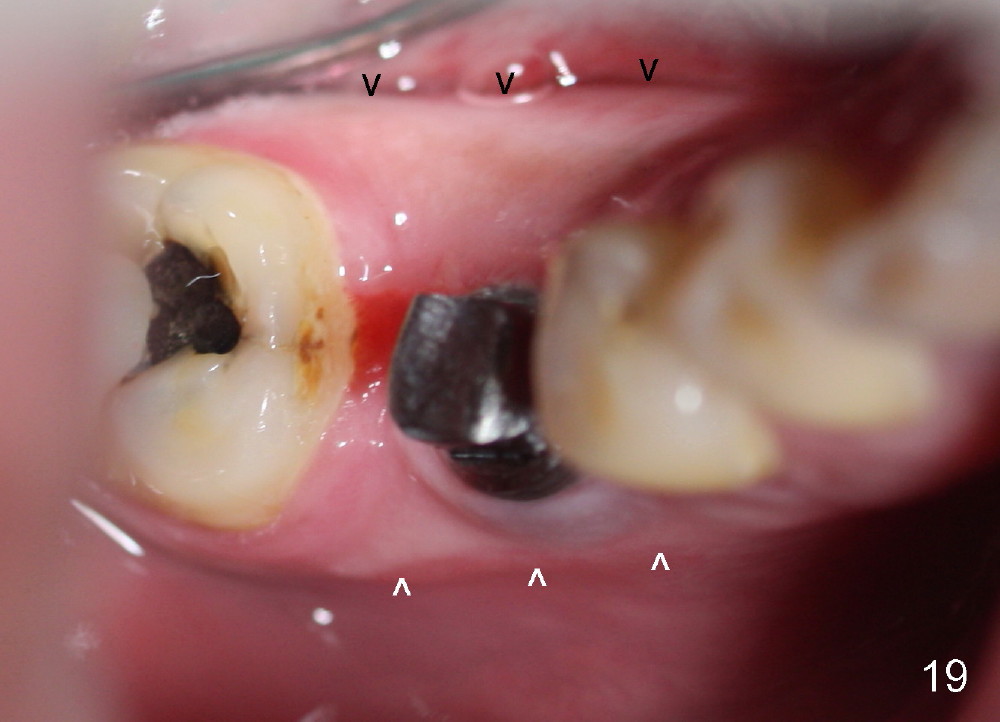

A 38-year-old lady agrees to have implant placement 7 years after loss of the crown of the lower right first molar (Fig.1,2). When the tooth is extracted, the septum is found to be low (Fig.3,4). To confirm it, a PA is taken (Fig.5). To initiate an osteotomy in the septum, it is trans-sectioned with thin osteotomes as shown in Fig.4 insert (black line). A 2 mm pilot drill is placed in the septum (Fig.6: P). The osteotomy is enlarged by 2.5-4.0 mm reamers (Fig.7,8), followed by insertion of 6x17 mm tapered tap at the depth 14 mm (Fig.9). The osteotomy is further enlarged by 4.5 and 5.0 mm reamers. A 6.0x14 mm one piece implant is placed initially. The trajectory is not ideal. A 6.0x14 mm one piece implant is placed initially. The trajectory is not ideal. The implant is removed from the osteotomy partially and reinserted with improved trajectory (Fig.11, compare to Fig.10 (red line)). Primary stability is high. There is not much bone mesiodistally so that the trajectory is easily changed in that direction. After abutment preparation, mixture of autogenous bone (harvested from reamers) and allograft is placed in the residual mesial and distal sockets (Fig.12). To contain the bone graft, an immediate provisional is placed (Fig.13 P). The occlusal plane of the provisional is significantly lower than that of the adjacent teeth to avoid micromovement of the implant. The patient is advised to eat soft food on the left side. Six days postop, the patient returns for prophy. The provisional is removed; the bone graft appears to be incorporating into the socket (Fig.14). After recementation, the provisional remains in place for 3.5 months; PA shows increased bone density in the mesial and distal sockets (Fig.15, compare to Fig.5,11). Due to insurance coverage, the patient defers fabrication of definitive restoration for at least 7 months. The immediate provisional is finally lost 8.5 months postop: the gingiva attaches to the 1-piece implant (Fig.16), while the density of the mesial socket increases (Fig.17 *) with formation of the cortex (lamina dura) coronally (v). Before the provisional (Fig.18 P) is removed for cementation of the definitive restoration, black shadow (*) is noted over the buccal gingiva. It is partially due to buccal placement (Fig.19) and partially due to buccal atrophy over a period of 10.5 months postop. How to prevent buccal placement? Positioning the first pilot drill in the septum buccolingually is a key. Eleven months post crown (Fig.20 C) cementation, the black shadow remains, but there is no tenderness. If the implant threads are immediately underneath the periosteum, there is tenderness.

CBCT taken 15 months post cementation shows that the implant is buccally placed (Fig.21 B), associated with possible postop buccal plate resorption (as compared to Fig.23 (coronal section of the site of #19). The buccal plate is not only thinner than the lingual one, but also concave (Fig.22 <). The tooth center (i.e., septum; Fig.23 T) is more buccally located than the center of the basal bone (B). Considering the denser bone lingually, the initial osteotomy should be more lingually (^). If the implant develops infection, it will be replaced by a more lingually placed implant (Fig.24 green).